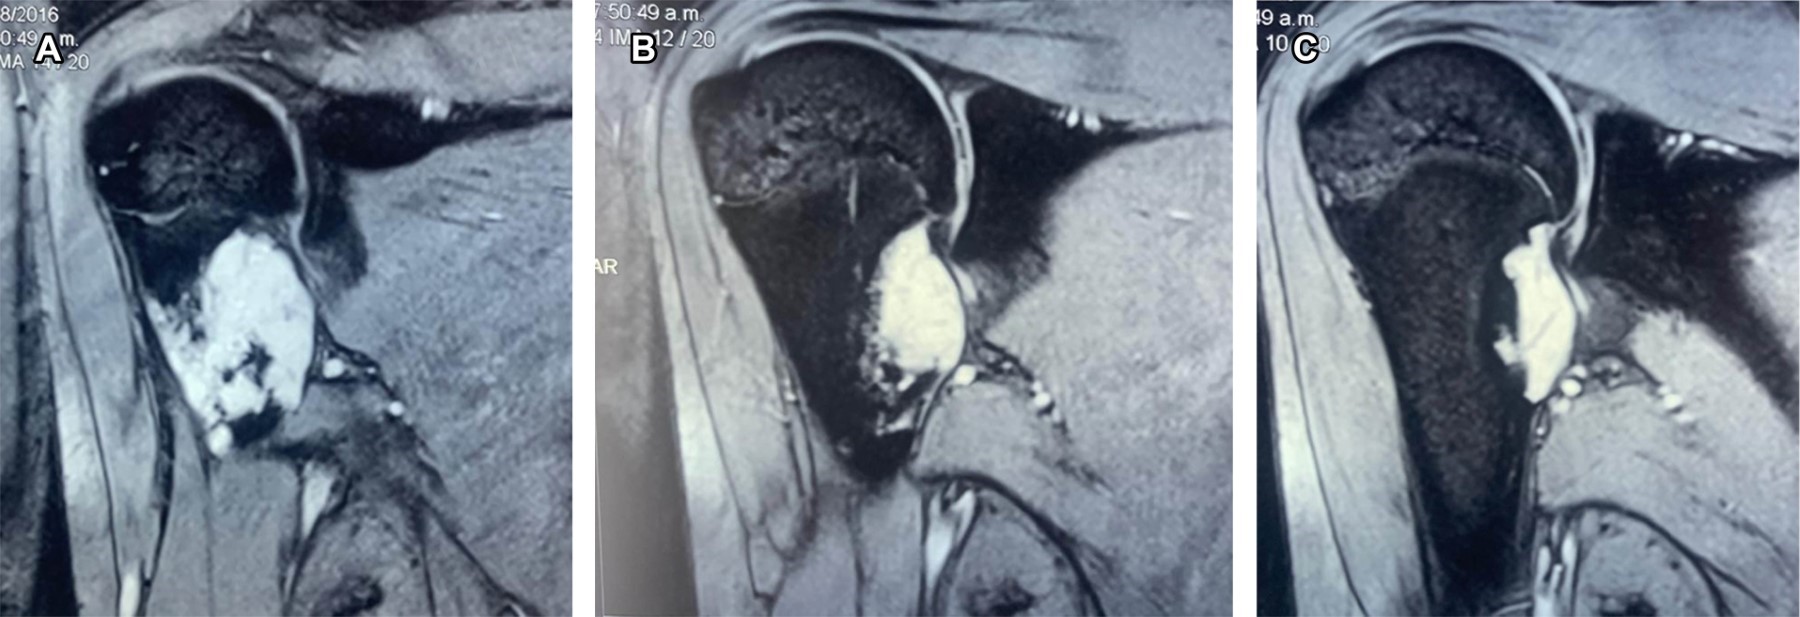

Osteochondroma is a benign tumor, defined as osteocartilaginous exostosis with corticomedullary continuity that reproduces the structure and progression of a physis during growth, considered a developmental disorder rather than a true neoplasia, caused by the separation of a cartilaginous fragment of epiphyseal growth, herniating through the normal bone surrounding the growth plate. It is observed in children and adolescents, without gender difference; most are solitary. The common sites of appearance are the distal end of the femur and the proximal end of the tibia and humerus; it can occur in any bone formed by endochondral ossification.

Figure 2